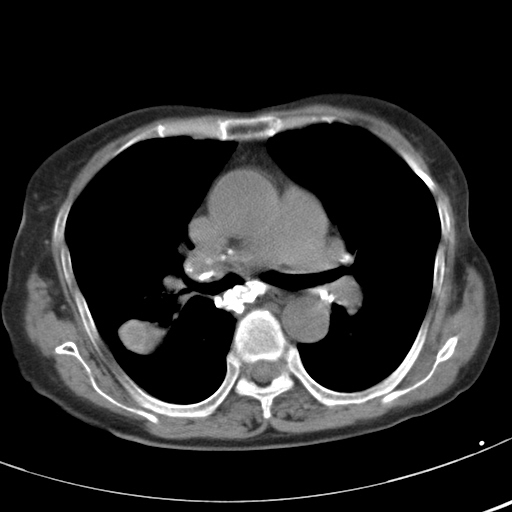

以下是引用hhcckk在2007-3-2 14:51:00的发言:[br]考虑结核球可能性大,依据[br]1病灶在下叶背段,结核的好发部位[br]2病灶内有大量的钙化,纵隔内有大量的淋巴结钙化[br]3重要的是半年前与现在相比无变化,假如是肿瘤的话不会这么‘善良’[br]4病灶周围卫星灶不明显,病灶有毛刺,胸膜凹陷,肿瘤不能完全排除,有条件的话最好做个活检

以下是引用liuyue在2007-3-2 17:15:00的发言:[br]1位置:右上叶后段[br]2性质:大分叶、粗长毛刺、条状斑片状钙化、纵隔多发淋巴结钙化,无强化,故考虑:肺结核灶(陈旧)